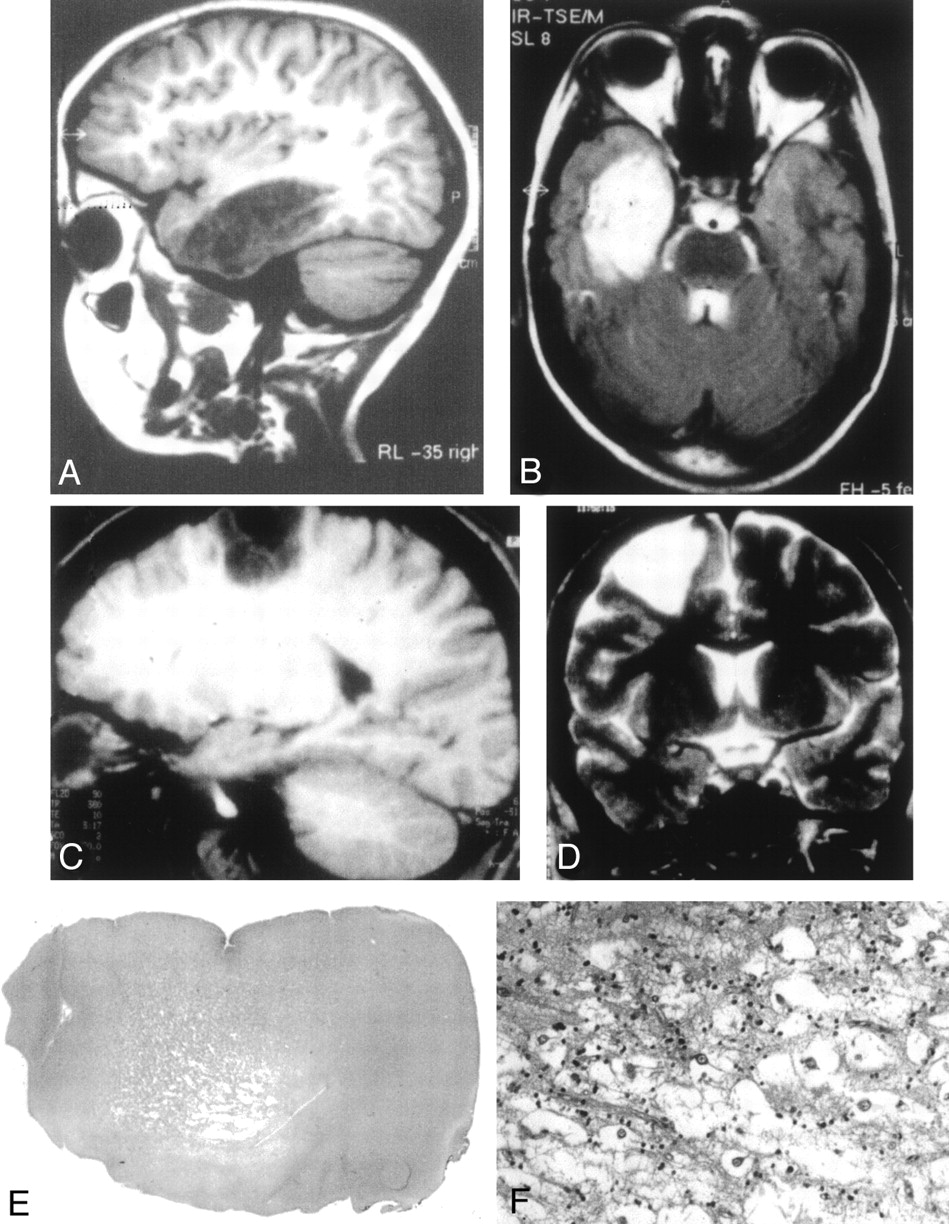

All cases displayed a cortical tumoral lesion that demonstrated neither perilesional edema nor mass effect on midline structures (Table 2, Figs 1A–D and 2A–D). Temporal, frontal, parietal, and occipital lobes were involved in six, seven, one, and one cases, respectively. One case (case 8) involved two adjacent lobes. On CT scans, the lesion appeared hypoattenuated in seven of eight available cases and heterogeneous in one case. No case demonstrated calcification, and two cases showed small cysts (cases 7 and 8). On T1-weighted images (Fig 1A), the lesion appeared to be hypointense in 13 cases and heterogeneous in one case (case 7). On T2-weighted images (Fig 1B), the lesion was of high signal intensity in all cases. A deformation of the overlying skull was observed in six cases. Gadolinium injection induced a tumor enhancement in three of 10 available cases, always with a nodular pattern. One of these cases had major hemorrhagic changes (case 7; Fig 2). In all cases, the lesion exceeded the thickness of the normal cortex and involved the white matter. In eight cases, the tumor width was maximal at the cortical level and decreased toward the ventricles, leading to a triangular pattern (Fig 1D) of distribution usually best seen on coronal images. The tumor boundaries were also rectilinear in three other cases but with a rectangular pattern (Fig 1C) of distribution, whereas the three remaining lesions were rounded. In all but two cases (cases 9 and 11), the lesion seemed to be divided by thin septa (Fig 1A–C). These septa were best seen on high-resolution MR images (inversion recovery 3-mm-thick sections, 3D T1-weighted images of 1-mm-thick sections) and had the same intensity as normal cortex. We named them “septations.” Consequently, most lesions were well-demarcated triangular lesions (57% of cases), did not display enhancement after contrast material injection (78% of cases), and showed septations (85% of cases). The association of these three features was observed in five (36%) of 14 cases.

Typical DNT findings.

A, Sagittal T1-weighted MR image shows a large lesion of low signal intensity involving the temporal lobe, without edema or mass effect and corresponding to a complex form of DNT. The lesion is divided by septations leading to an alveolar aspect.

B, The lesion is of high signal intensity on this T2-weighted MR image. The septations appear to be of low signal intensity.

C, Sagittal T1-weighted MR image shows a frontoparietal DNT with sharp boundaries and a rectangular pattern of distribution.

D, Coronal T2-weighted MR image illustrates the triangular pattern of distribution typical of DNT, with a tumor width that is maximal at the cortical level and decreases toward brain ventricles.

E, Low-magnification view showing the cortical location and the nodular architecture typical of DNT (hematoxylin phloxin-saffron, magnification ×10).

F, The glio-neuronal specific element is composed of oligodendrocyte-like cells surrounding areas of mucoid substance containing “floating neurons” (hematoxylin phloxin-saffron, magnification ×300).